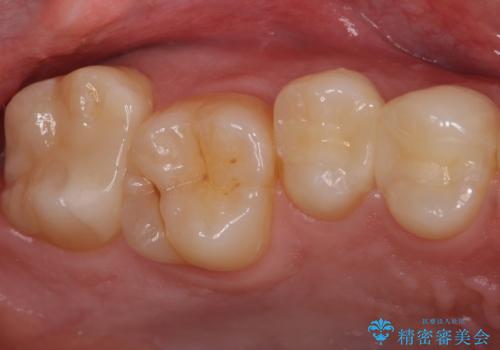

虫歯の除去後セラミックインレーでの修復処置をしていきます。

- 右上457 セラミックインレー 77,000円×3本費用は治療当時の料金となります

歯と歯の間は虫歯の好発部位とされています。

適合の良いインレーでの修復をすることで再発を防止します。